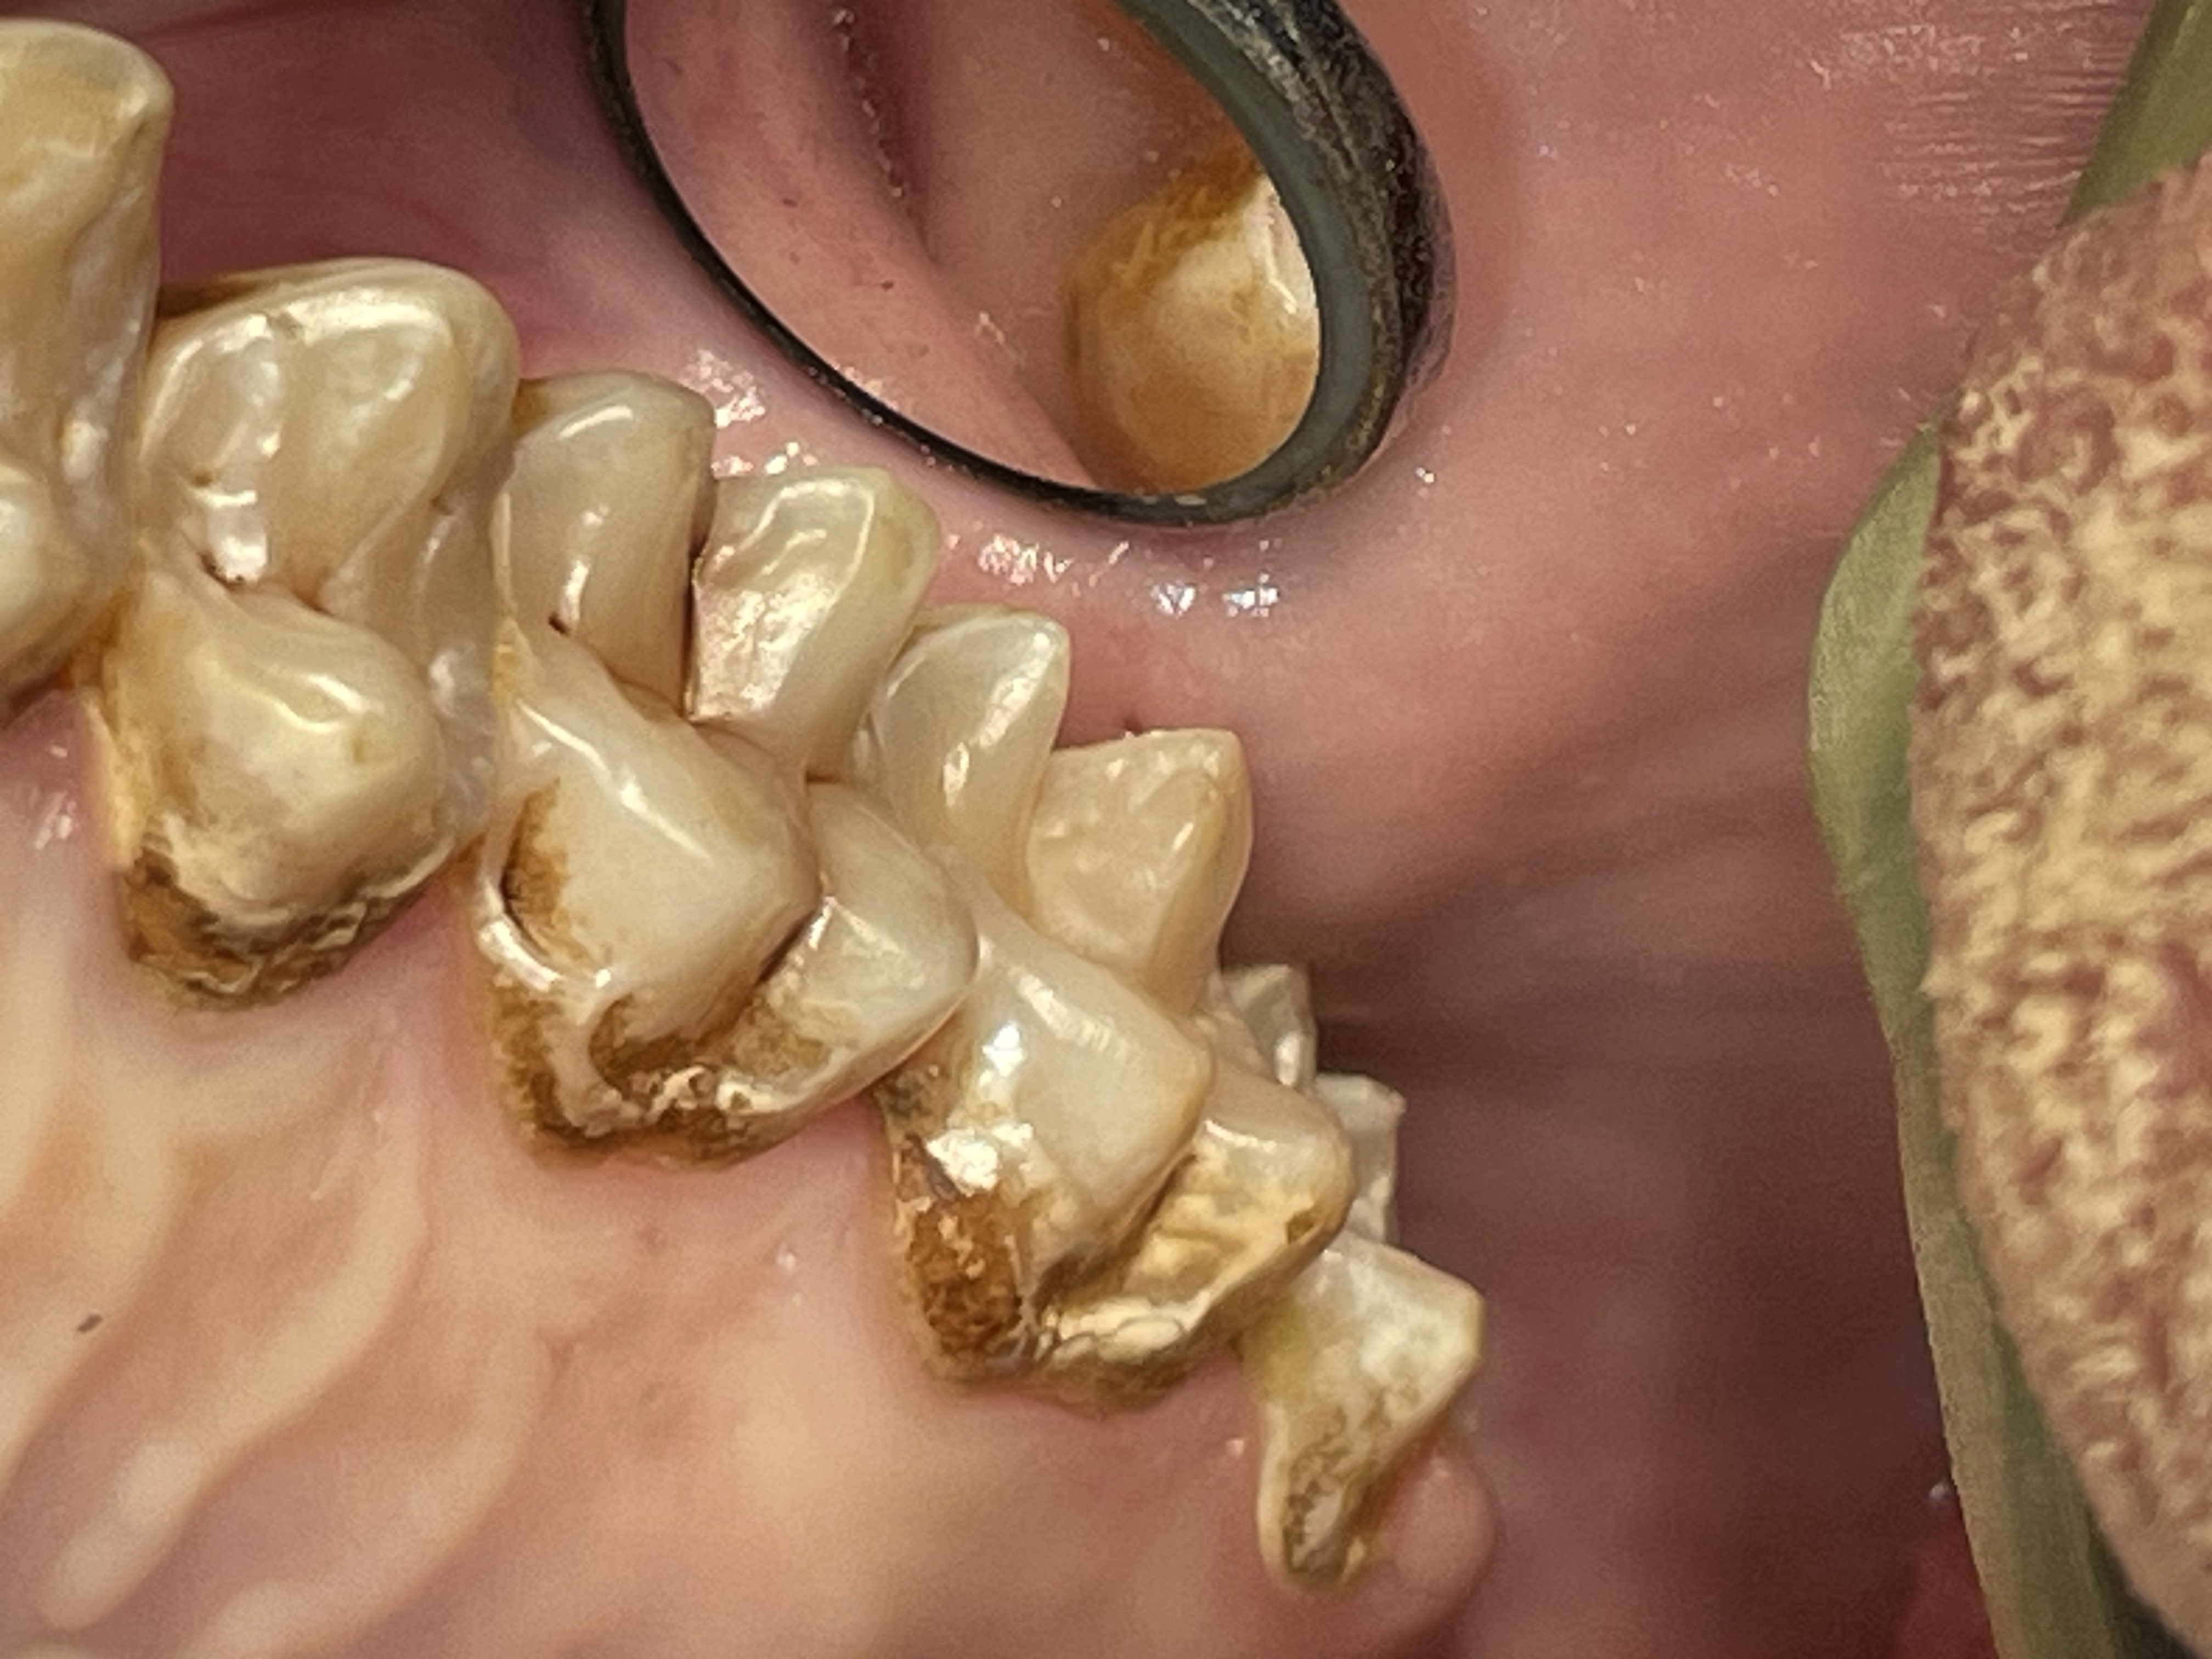

Most or our orangutans however, have had chronic, serious periodontal disease. All of our males have eventually lost all their teeth due to periodontal disease. That has not been the case with the females. We are not the only zoo that has had the chronic periodontal problems with orangutans. See Dr. Norm Stollers' paper: In the typical orangutan case that I have dealt with, there is not much accumulation of plaque or calculus. However, deep periodontal pocketing and bone loss progresses until the teeth become very mobile. I have not observed much bleeding in the most severe of these cases. We discussed preventive strategies and even tried chlorhexidine gluconate rinses to subdue the disease process. However, the orangs did not accept the products, probably due to the taste.

I believe that there is very likely some genetic component to the periodontal disease prevalence in our orangutan lineage. Most of them that we have had are crosses of Sumatran and Borneo genetic lines. And again, with what I have been able to learn about their wild diets is that it is very different than what can be offered in captivity in this part of the world.

Enamel erosion throughout dentition due to chronic regurgitation/ingestion behavior